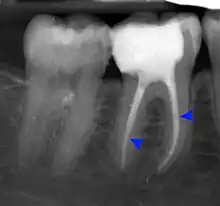

Pressure or pain in the jaw area can be associated with dilaceration. Checking in with a general dentist and an endodontist should be done if a patient feels these symptoms.[4] Signs in radiographic imaging will indicate a bend in the tooth's root as opposed to a straight growth.[1] Dilaceration of the crown, the top part of the teeth that we see when we smile, can be visually seen for diagnosis. Crown dilaceration will present itself as a tooth that is angled to face outward or inward. It will be a non axial displacement and more of a longitudinal displacement.[5]

Dilaceration can be diagnosed with a simple radiograph of the affected teeth. However, if the bends are more lingual or facially present,[1] more advance imaging techniques may be necessary. In some cases a cone-bean CT scan may be useful to create a three dimensional view.[9]